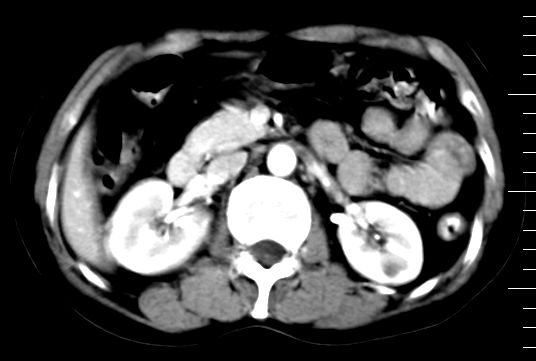

标题: CT10752:F,52岁,反复上腹部疼痛,平扫+增强. [打印本页]

f、52岁,反复上腹部疼痛2年。肺结核病史10多年,胸片双上肺结核纤维化。

双肾灌注良好,代谢增快,动脉期肾盂见造影剂,左肾下极背侧见一略低密度病灶,延迟期见似不强化囊肿,双侧肾上腺未见异常。

3、左肾下极低密度灶,考虑囊肿可能性大,建议随访,除外小肾癌(无强化可以基本除外)。

5.增强,脾特别明显是怎么回事?